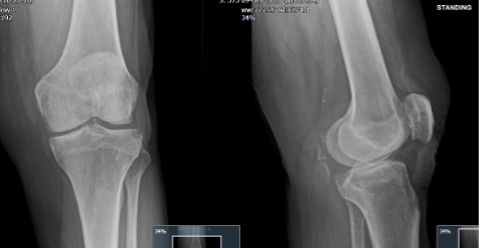

X-ray films

(see above)

..showed only mild decreased medial joint space

(with some vascular calcification posteriorly)

That joint space or gap between the bones, tells us us Mr D is a little way off joint replacement.

Knee: OA, meniscus + ligament knee => some catching but mainly aching pain on the inside, with OA that ain’t that bad on X-ray films